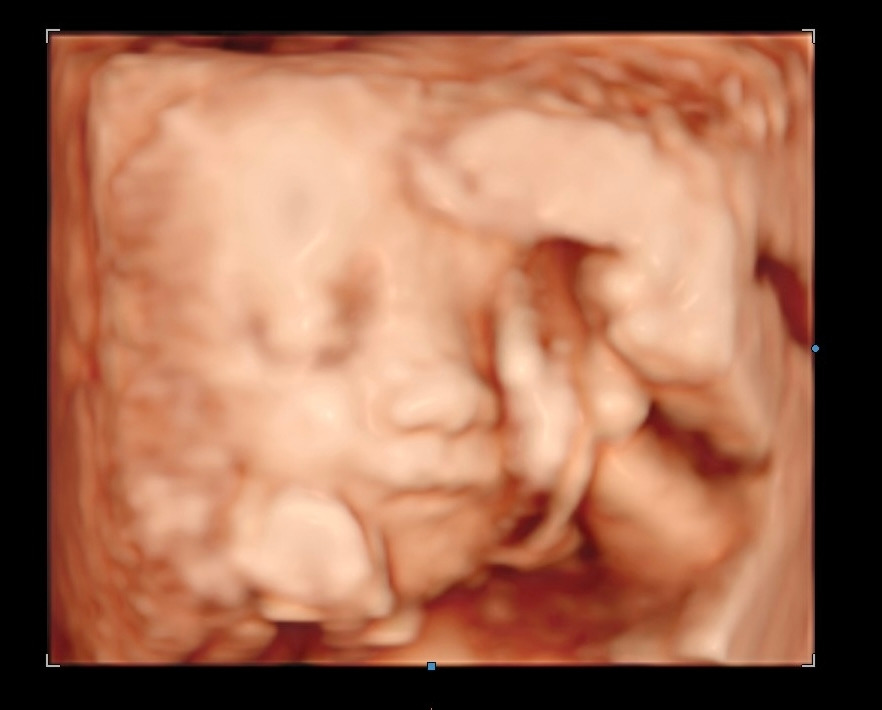

유럽 병원에선 태아 초음파도 자주 보지 않고 대충 본다. 의지의 한국인은 기어코 사설 기관을 찾아내 3D 초음파 사진을 찍었다